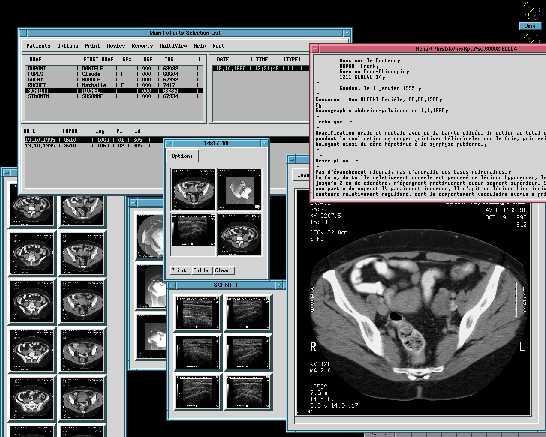

Esto es lo que dije a un amigo suizo que me llamo aqui en España, este explotaba Solaris, X11R4 y Motif 1.1 para los PC's, cada licencia le costaba la bagatela de 8.000 dolares y estaba buscando algo "mas barato", le comente el coste de Linux, no me colgo el telefono porque me tiene aprecio, pero si que me dijo algo que sonaba a "borracho", el caso es que lo compro. Este buen hombre posee una empressa (DAPSYS. SA ) dedicada a la informatica hospitalaria, su especilidad es el archivado de imagenes radiologicas y su restitucion en pantalla, sea con X11 y Motif o Win95.

Esta empresa tenia unas pocas instalaciones ya realizadas en Suiza, cuando de Canada se les presento un dia (casi sin avisar) dos vendedores de una muy importante empresa americana, estos no venian a vender sino comprobar "algo" que "alguien" les habia comentado en el RSNA de Chicago, el RSNA es el evento mundial en el tema de la radiologia. Dos meses despues el director de Dapsys se fue hacia Montreal con su "portatil" para enseñar el producto a unos cuantos doctores, tres meses despues (y 504 años despues de Colon) llego yo a las Americas para hacer la primera instalacion en aquel continente de Iris. Iris es la aplicacion de archivado y restitucion de imagenes radiologicas.

Ademas Iris permite centralizar por paciente TODOS los eventos radiologicos, cada imagen tiene grabada en ella el nombre, apellidos y codigo de paciente, Iris es capaz, mediante tratamiento OCR, extaer esos datos de la imagen y archivar la o las imagenes del paciente junto a las existentes (de haberlas).

Para un paciente determinado se pueden presentar X exploraciones de varias modalidades. Una exploracion es un examen radiologico, un examen puede tener una o X imagenes o disparos. Una modalidad es un aparato capaz de producir imagenes radiologicas sea por Rayos-X, ultrasonidos, resonancia magnetica, etc...

Cuando se producen las imagenes estas llegan directamente al servidor, este tiene que ser capaz de "leer" la imagen y extraer los datos del paciente, para reenviar "rebotar" la imagen a las estaciones de visualizacion y archivar con los datos del paciente leido, para poder devolver la o las imagenes en peticiones posteriores.

Antes de archivar una imagen esta pasa por un proceso de "limpieza" y compresion no destructiva. Conseguimos ratios de 60% en compresiones, podriamos llegar a mas pero seria en detrimento de la eficacia tanto en el archivado como en la posterior restitucion.

Segun las pruebas realizadas una imagen de 512x512x2 tarda 0.3 segundos, de promedio, en mostrarse en pantalla desde que se inicio la transaccion. Hablo de promedio, porque un estudio no es siempre una sola imagen, este promedio es mejorable y no solo por hard sino por la propia forma de obtenerlo.

St.John tiene 12 salas que suelen producir unas 1.000 imagenes al dia, esto da un poco a que se tienen que esperar los dos servidores, durante el periodo de pruebas estamos llegando a la friolera ocupacion de CPU del 2%, con 6 salas enviando imagenes.

Las SGI reciben las imagenes que "rebotan" en los servidores, de esta forma los radilogos tienen a disposicion las imagenes "del dia". Estas estaciones no son nuestras, ni son Linux (pero poco les queda :-), estas estaciones tiene 2 pantallas de 20 pulgadas cada una.

Las estaciones de trabajo IRIS/Motif son para hacer una labor de, principalmente, de visualizacion con diagnostico, gracias que pueden pilotar hasta cuatro pantallas, de momento solo tienen 2 de 20 pulgadas, las busquedas en la base de datos se pueden resumir en :